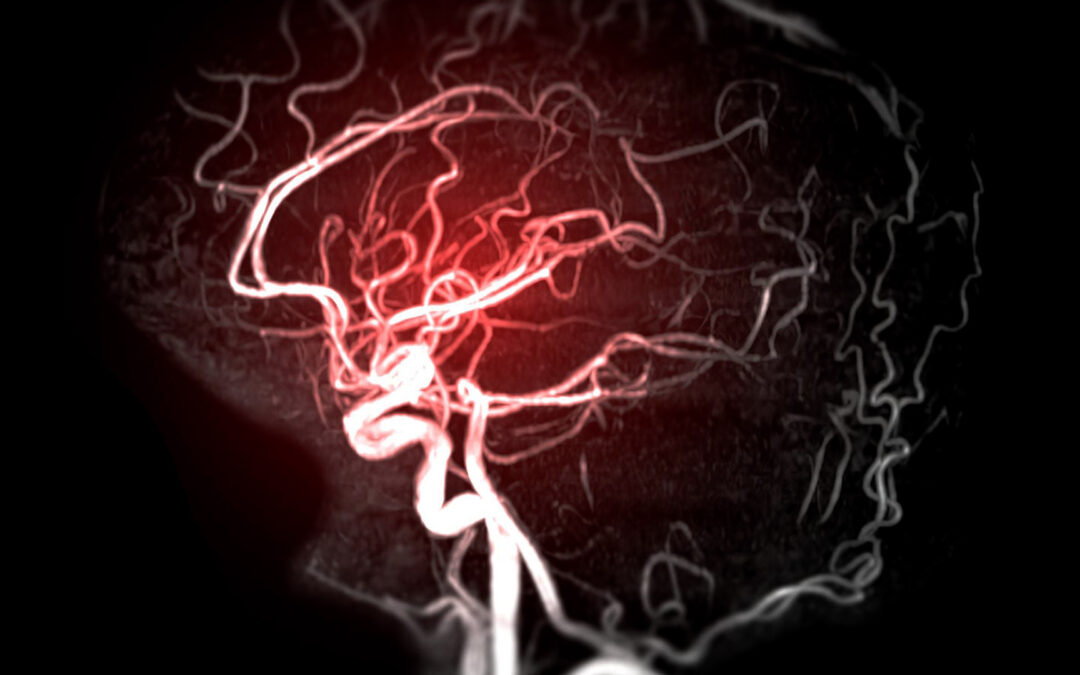

A brain aneurysm is a weak spot in a blood vessel in the brain that bulges or balloons outward. While many aneurysms remain small and asymptomatic, others can rupture, leading to a life-threatening condition known as a subarachnoid hemorrhage. Understand the signs and...